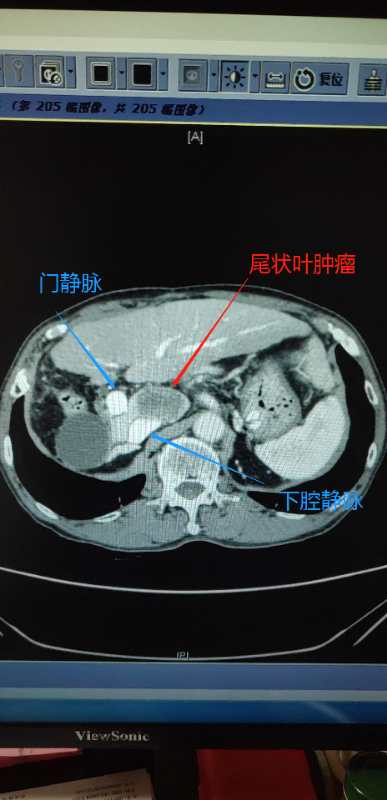

肝尾状叶肿瘤

巨大肝脏尾状叶肿瘤——全尾叶切除 下腔静脉部分切除 下腔静脉重建